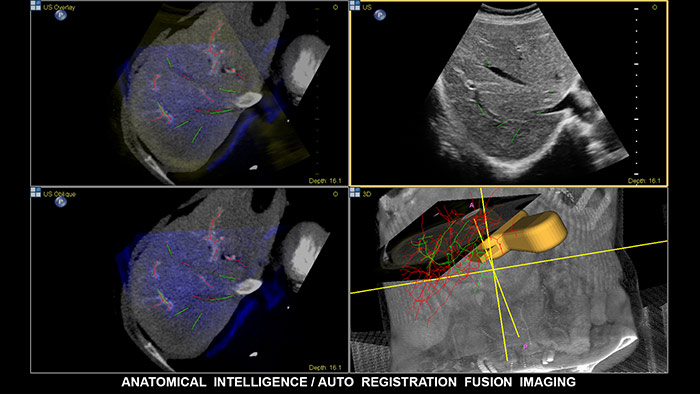

Fusión de imágenes y navegación

La fusión de imágenes combina las ventajas inherentes de la adquisición de imágenes de multimodalidad directamente en el sistema de ultrasonidos mediante seguimiento electromagnético. Al combinar TC/RM/PET con ultrasonidos en tiempo real y la posición en tiempo real del paciente, el profesional sanitario cuenta con una potente herramienta de diagnóstico y, al mismo tiempo, limita la radiación debido a que se necesitan menos exploraciones de confirmación; de este modo, se potencia la productividad del departamento.  EPIQ, con su exclusivo sistema de ultrasonidos con inteligencia anatómica (AIUS), ofrece fusión de imágenes con registro automático de volúmenes de TC/RM y ultrasonidos, tarea para la que se emplea una décima parte del tiempo que suele durar la alineación.  La navegación guiada por aguja es una herramienta que mejora el rendimiento en las intervenciones hepáticas más complejas; además, se ha demostrado que mejora el flujo de trabajo y reduce la exposición a la radiación al necesitarse menos exploraciones de confirmación.  EPIQ de Philips incluye una gama completa de soluciones, entre las que cabe destacar las siguientes: CIVCO eTrax™, el localizador de aguja adaptativo de Philips y los localizadores de aguja coaxial de Philips. De esta manera, el profesional sanitario, al disponer de una compatibilidad tan amplia con los dispositivos de biopsia y ablación, es libre de elegir las mejores herramientas para el procedimiento en función del grado de complejidad.

Fusión y navegación

Tome decisiones con seguridad incluso en casos diagnósticos complicados con ayuda de las funciones de fusión de imágenes y navegación guiada por imagen de Philips. El flujo de trabajo agilizado permite que los profesionales sanitarios consigan una fusión eficaz de TC/RM/PET con ultrasonidos en tiempo real; a su vez, la navegación guiada por aguja ayuda a guiar la biopsia de lesiones pequeñas y de difícil acceso.